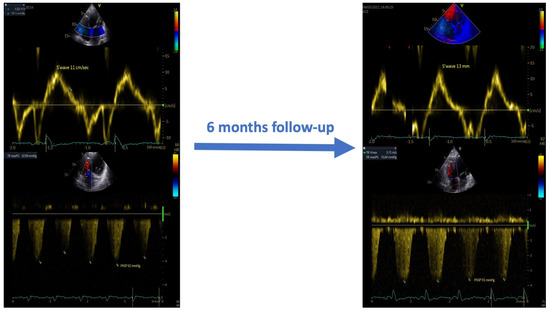

In addition, as shown in Table 2 and Figure 3, at the six-month follow-up, the CCM therapy induced right ventricular reverse remodeling and reduced systolic pulmonary pressure values.

Figure 3.

Effects of CCM therapy on the systolic function and pulmonary artery systolic pressure at the six-month follow-up.